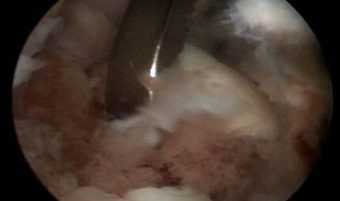

Cirugía de liberación de adherencias (cicatrices) dentro del codo que se produjeron posterior a una fractura del codo